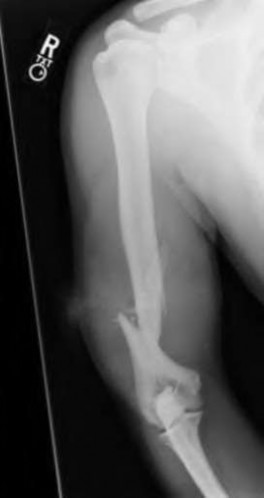

A 20-year-old park ranger trips and falls onto his right wrist with the wrist in extension and pronation. The local urgent care orders both radiographs and a CT, which you review and determine to be normal. The patient complains of ulnar-sided wrist pain. On exam, his tenderness is localized to the fovea. Ulnar deviation also causes him pain. There is no snapping sensation with wrist supination, flexion, and ulnar deviation. He otherwise has 5/5 strength to his first dorsal interosseous muscle with 4mm static two-point discrimination on the ulnar side of the 4th digit. Which of the following injuries is most likely responsible for his symptoms and exam?